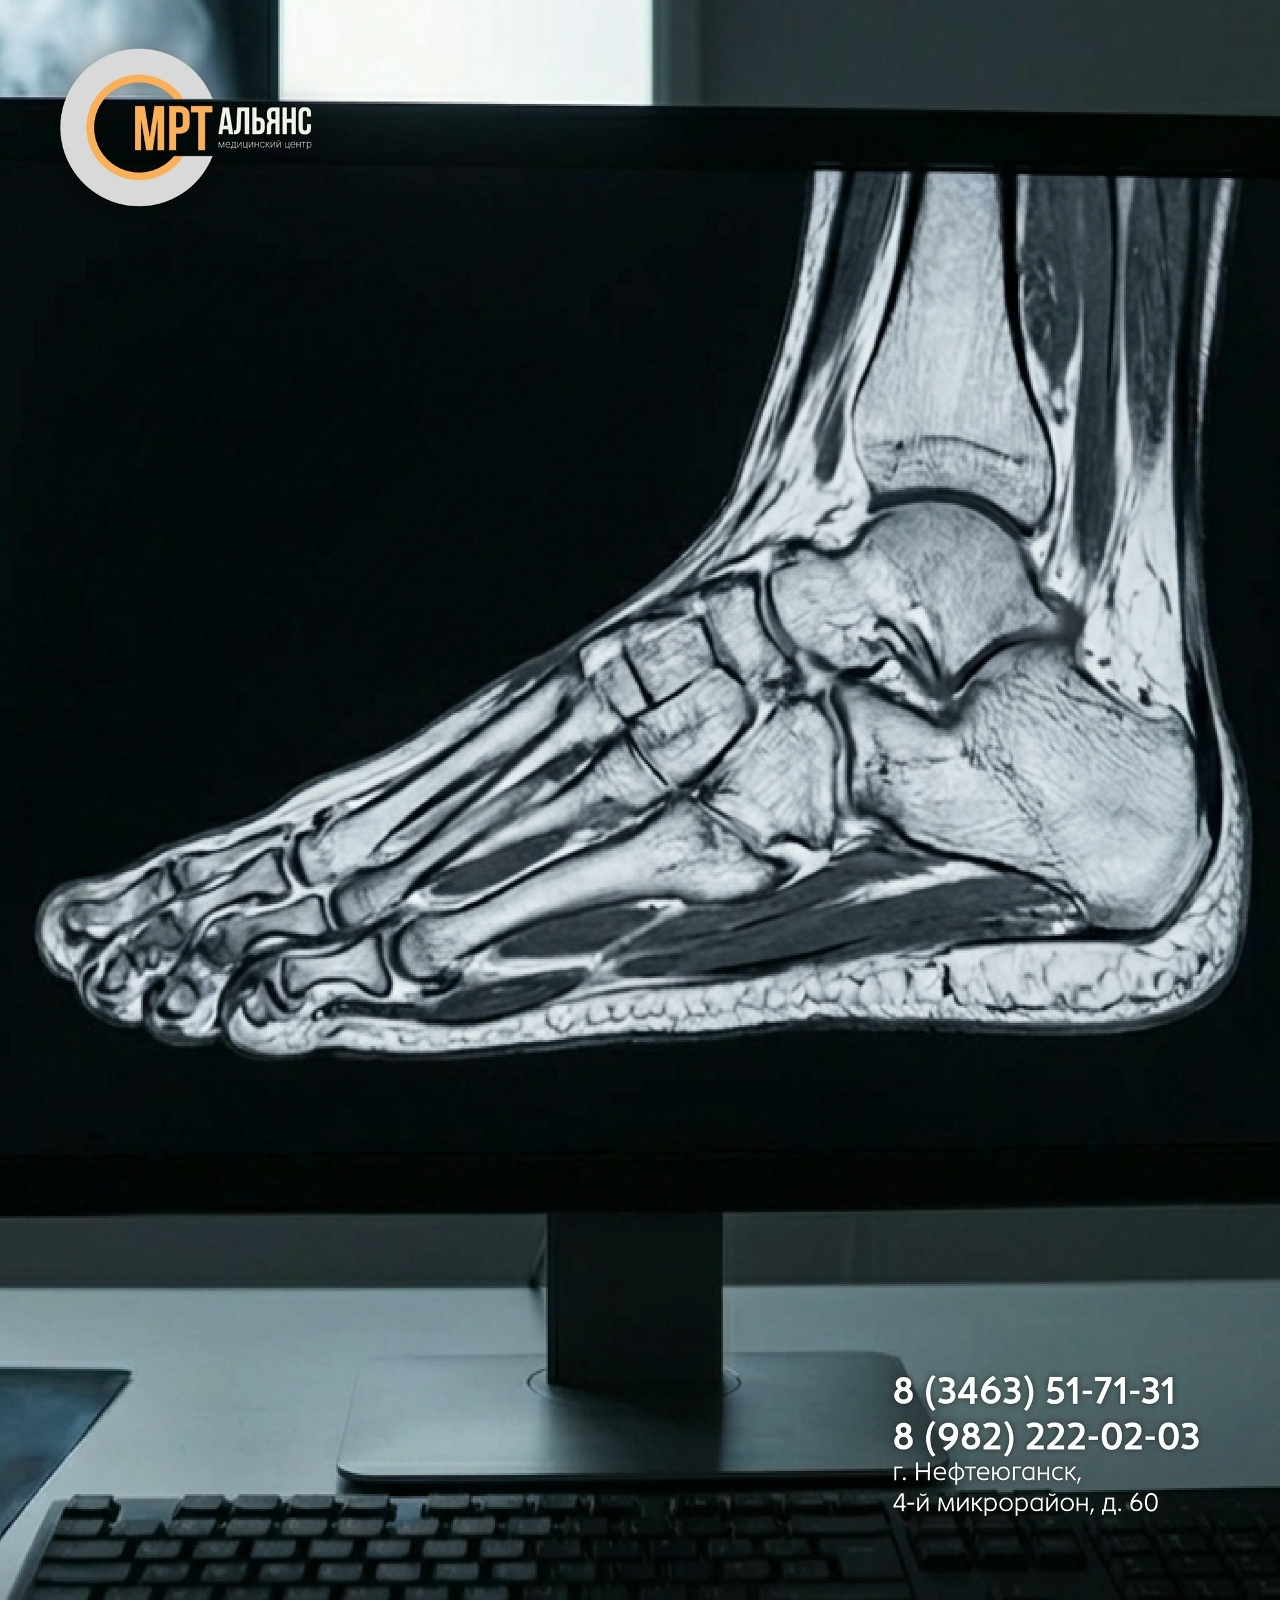

Это не просто «снимок». Это возможность определить:

— истинную причину боли при ходьбе или нагрузке

— степень повреждения после травмы, даже если рентген «чист»

— ранние признаки дегенеративных изменений до появления выраженных симптомов

— источник воспаления или подозрение на новообразование без инвазивных процедур

МРТ стопы показана при подозрении на повреждения связок и сухожилий, болевом синдроме неясной этиологии, планировании оперативного вмешательства или контроле эффективности консервативного лечения!